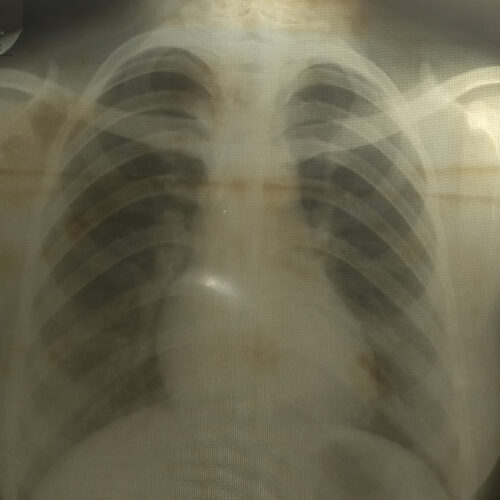

海外出国 に「レントゲン写真」が必携だった !?

「海外旅行」は、現在でも多くの人にとって大きなイベントかと思います。しかし、かつてに比べれば、ずいぶん身近なものになっているのではないでしょうか。一般の方でも、夏休みなどの長期休暇や、卒業旅行など、あるい社用での海外出張などで海外に行く... 昭和 懐古